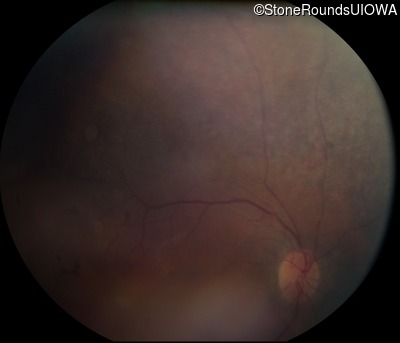

Fundus Photography - Right - 20/50 -3

Exemplar